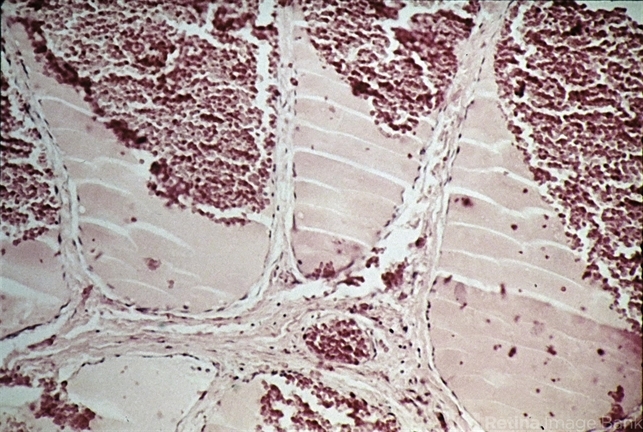

- cavernous hemangioma of the retina, tumor, endothelium

- Cavernous hemangioma. Microscopic appearance. Tumor shows large, blood-filled spaces separated by endothelium-lined fibrous septa (H&E x lOl).